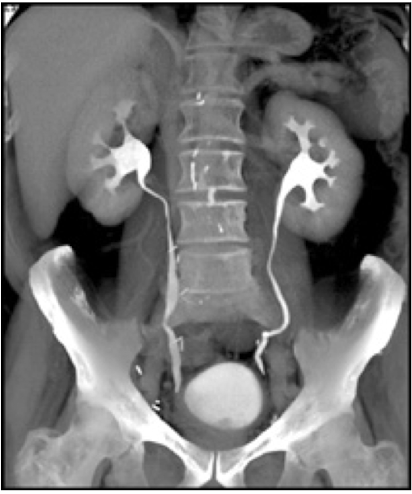

IVP (IV pyelogram)

XRAY using IV contrast material to assess kidney, ureters and bladder (less commonly used)

*CT Urogram is more common for assessing flank pain

Abdominal Radiograph

CT urography

CT scan using an IV contrast material to assess kidney, ureters, and bladder

Abdominal Radiograph